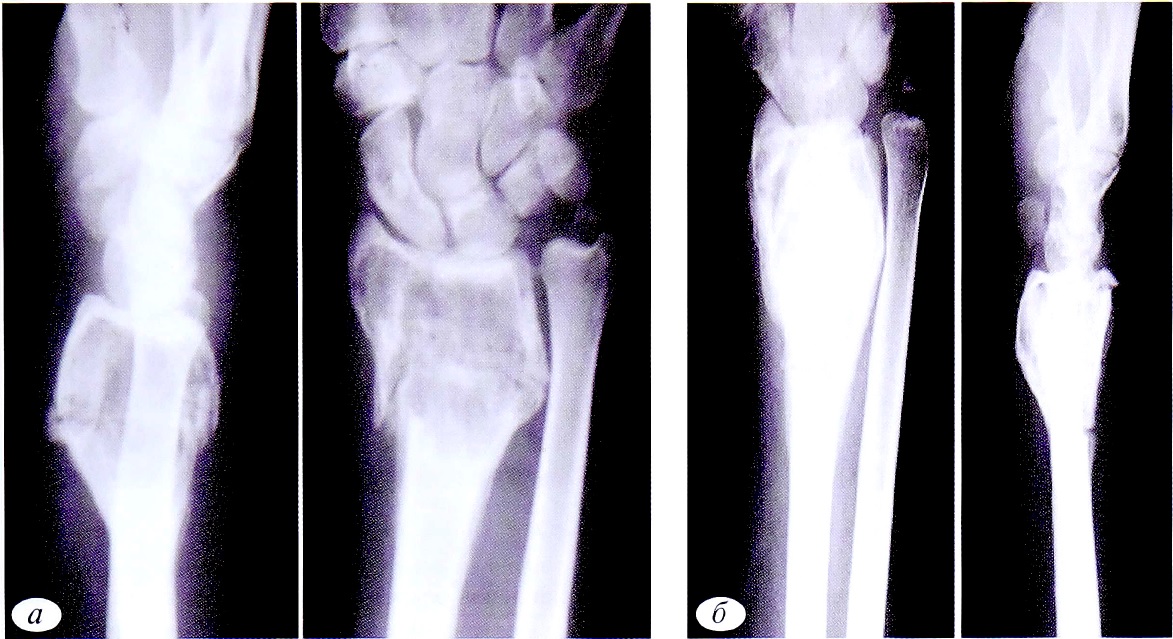

Рентгенологическое исследование позволяет выявить локализацию и характер перелома. Рентгенологическое обследование начинали после клинического осмотра и уточнения области исследования. Объем обследования определяли исходя из жалоб, клинической картины и допустимых доз облучения (для детей) (рис. 1).

Рис. 1. Пациент К.,9 лет. Диагноз: патологический перелом левой плечевой кости на фоне кисты кости. Рентгенограммы левой плечевой кости в гипсовой повязке (а), через 6 нед после снятия гипсовой повязки (б): отмечаются консолидация перелома и признаки репарации кисты кости.

Fig. 1. Patient К.,9 years old. Diagnosis: Pathological fracture of the left humerus due to bone cysts. a — radiograph of the left humerus in a plaster cast; б — radiograph of the left humerus 6 weeks after removal of the plaster cast. X-ray consolidation of the fracture, and signs of repair of the bone cyst.